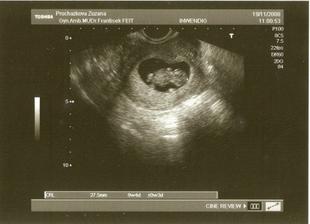

Ve 13. týdnu jsme absolvovali první screeningové vyšetření v Olomouci, všechno bylo dle doktora v pořádku, tak jsme si oddechli. Dokonce jsme se již tak brzy dozvěděli, že čekáme chlapečka. Sice jsem víc toužila po té kouzelné princezně🙂 ale hlavně, že je miminko v pořádku. Manžel říkal, že holčička vyjde napodruhé🙂 Tak mu budu teda věřit......................

Ve 20. týdnu (20. ledna 2009) jsme už i s tatínkem dorazili na druhý genetický screening. Pan doktor nám měřil hlavičku, nožičky a ukazoval všechny orgány, srdíčko, ledviny, moč. měchířek atd. Dokonce jsme slyšeli i srdíčko...nezapomenutelný zážitek. A prý je to zase všechno v pořádku...měli jsme oba radost, a doufáme, že i nadále to bude vše probíhat tak jak má...........................2.3. nás pan doktor (asi preventivně🙂) vystrašil s předčasným porodem, předepsal nám Magnosolv a zakázal jakýkoliv procházky a fyzickou aktivitu. Takže teď budu čtrnáct dní do další kontroly odpovědně ležet a odpočívat.........................16.3. kontrola...pan doktor nás pochválil, že je vidět jak pěkně jsem odpočívala, čípek se prodloužil o 5 mm, což je super, malej je již hlavičkou dolů (ale to nemusí být konečná🙂)..........................Dne 19.3. (28. tt) nás čeká zátěžový test na těhu cukrovku, brrrrr......................Výsledky testu na cuktovku jsou v normě, nemusíme držet žádnou dietu...ikdyž celkem jsem už přibrala 11 kg, takže by to nebylo špatné🙂.....................15.4. další poradna, teď už pořád po 14 dnech, a tak dlouho očekávaný velký ultrazvuk. Byla to paráda, vážíme 1600 g, ale jsme zase otočení prcinou dolů, takže přání maminky, aby malej zůstal už tak jak má, nebylo vyslyšeno, malej se prostě otáčí jak se mu zachce. Podle pana doktora máme malýho artistu🙂 Každých 14 dní jsme totiž otočení jinak...tak snad příště už to bude správně a napořád..........................11.5. první monitor miminka, vše je v pořádku, otočení jsme správně, Ondrášek už má 2600 g............................15.5. druhý monitor, opět ještě u svého mudr., neotočili jsme se, takže teď už to bude hlavičkou dolů až do konce. Už se nám to prý chystá, malej se tlačí dolů. Tak jsem zvědavá za jak dlouho budeme rodit....Dnes 16.5. jdeme na svatbu kamarádky, tak doufám, že dnes to teda nebude🙂